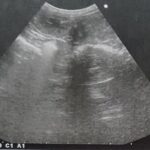

甲状腺機能低下症ってまじヤバい 2026/4/2 Kir, シュナウザー一週間経ったのでキルルンのエコーを再度撮りに。 子宮に無菌の水が溜まっているらしい。水というかもっと粘度の高いものだけど。 ...